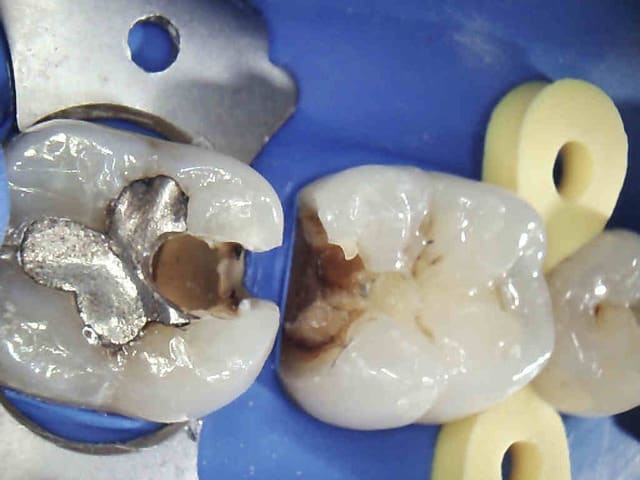

exemple :

Mobilité 31 (motif de la consultation); plan d'occlusion HS ( égression ).

Patient n'ayant pas 10 balles (mais qui travaille pourtant mais au smic malgré la moitié de cotisations sociales il a peanuts de remboursements) avec une mutuelle de merde en plus.

Amusez vous bien.

Ben, totale et subtotale. Hey, what did you expect?

Endos + raser le secteur postérieur haut, rétablissement d'un plan d'occlusion correct avec de la fixe + Stellite bas.

Ca durera bien quelques années.